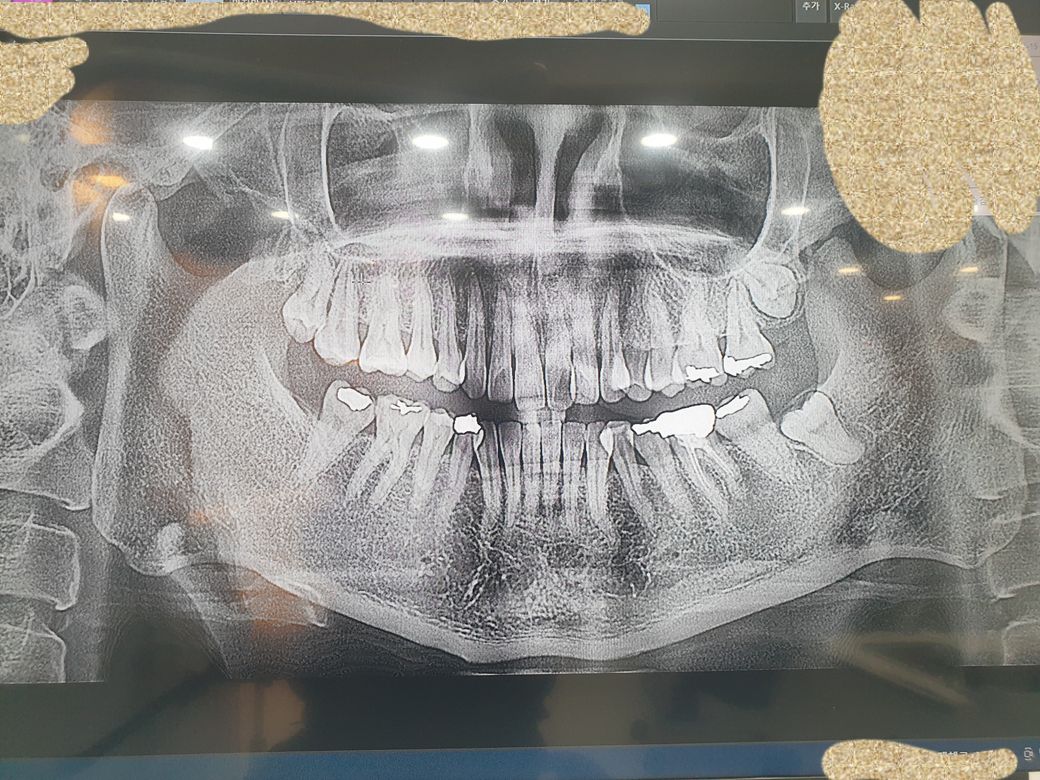

왼쪽 어금니 치근단수술 꼭 전신마취해야하나요?

왼쪽 신경치료후 크라운씌운 어금니아래 고름주머니가 다시 재발했습니다.1cm정도크기입니다.

예전에는 이것보다 더 큰사이즈였는데 부분마취로

구강악안면외과에서 수술했구요. 재발입니다 ㅜ

사진으로 봤을때 낭종이 경계부위가 하치조 신경과 가까울 가능성이 있기 때문에 신경손상의 가능성이 있어요.

1) x ray 사진상으로 보아 치근단 병소의 범위가 커 보입니다.

보존과에서도 수술하기도 합니다. 전신마취를 하느냐 부분마취를 하느냐의 문제는 수술의 난이도

치근단 병소의 크기에 따라 달라집니다.